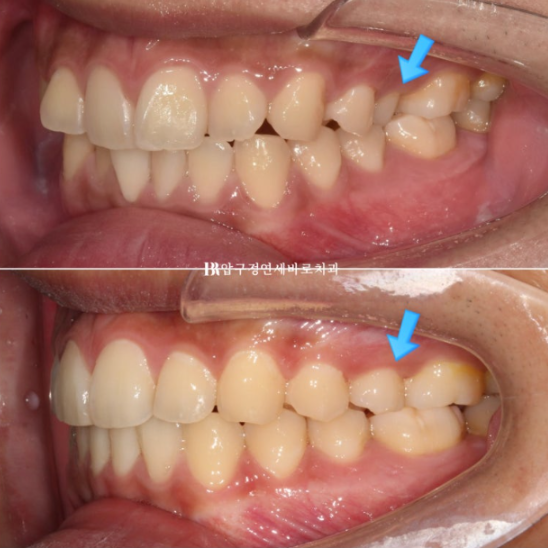

23.12

파란 화살표 어금니는 아래 어금니와 거꾸로 물리는 반대교합 입니다.

파란 화살표 반대교합도 해소가 되었습니다

23.12~24.10